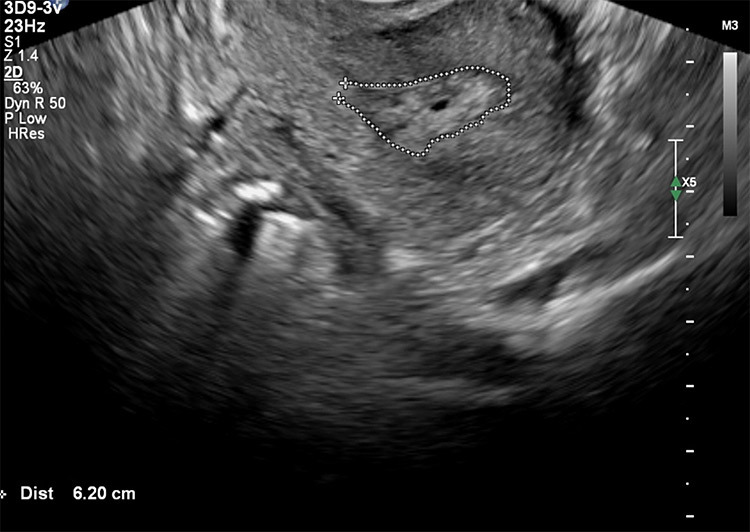

Οι παρακάτω τέσσερις εικόνες δείχνουν:

Δυο υπερηχογραφικές μελέτες πολύποδα και πώς διερευνάμε το ενδομήτριο ( 1 και 2 )

Η υδρο-υπερηχογραφία, είναι μια προχωρημένης τεχνολογίας τεχνική υπερηχογράφησης όπου εγχέεται φυσιολογικός ορός διαμέσου τραχηλικού καθετήρα, στην ενδομητρική κοιλότητα για να βελτιώσει την απεικόνιση. Επειδή το υγρό φαίνεται μαύρο στο υπέρηχο οι επιφάνειες των εσωτερικών ανωμαλιών και πολυπόδων διαχωρίζονται και μπορούν να μετρηθούν αλλά και να χαρτογραφηθούν με μεγαλύτερη ευκρίνεια. Αυτή η μέθοδος βελτιώνει την εκτίμηση της ενδομητρικής κοιλότητας, καθιστώντας ευκολότερη την ανίχνευση και τη μέτρηση των πολυπόδων με ακρίβεια. Η υδρο-υπερηχογραφία είναι ιδιαίτερα ευεργετική για τη διάκριση των πολυπόδων από άλλες ενδομήτριες παθολογίες, παρέχοντας μια καθαρότερη και πιο λεπτομερή αξιολόγηση σε σύγκριση με το απλό δισδιάστατο γυναικολογικό υπερηχογράφημα.